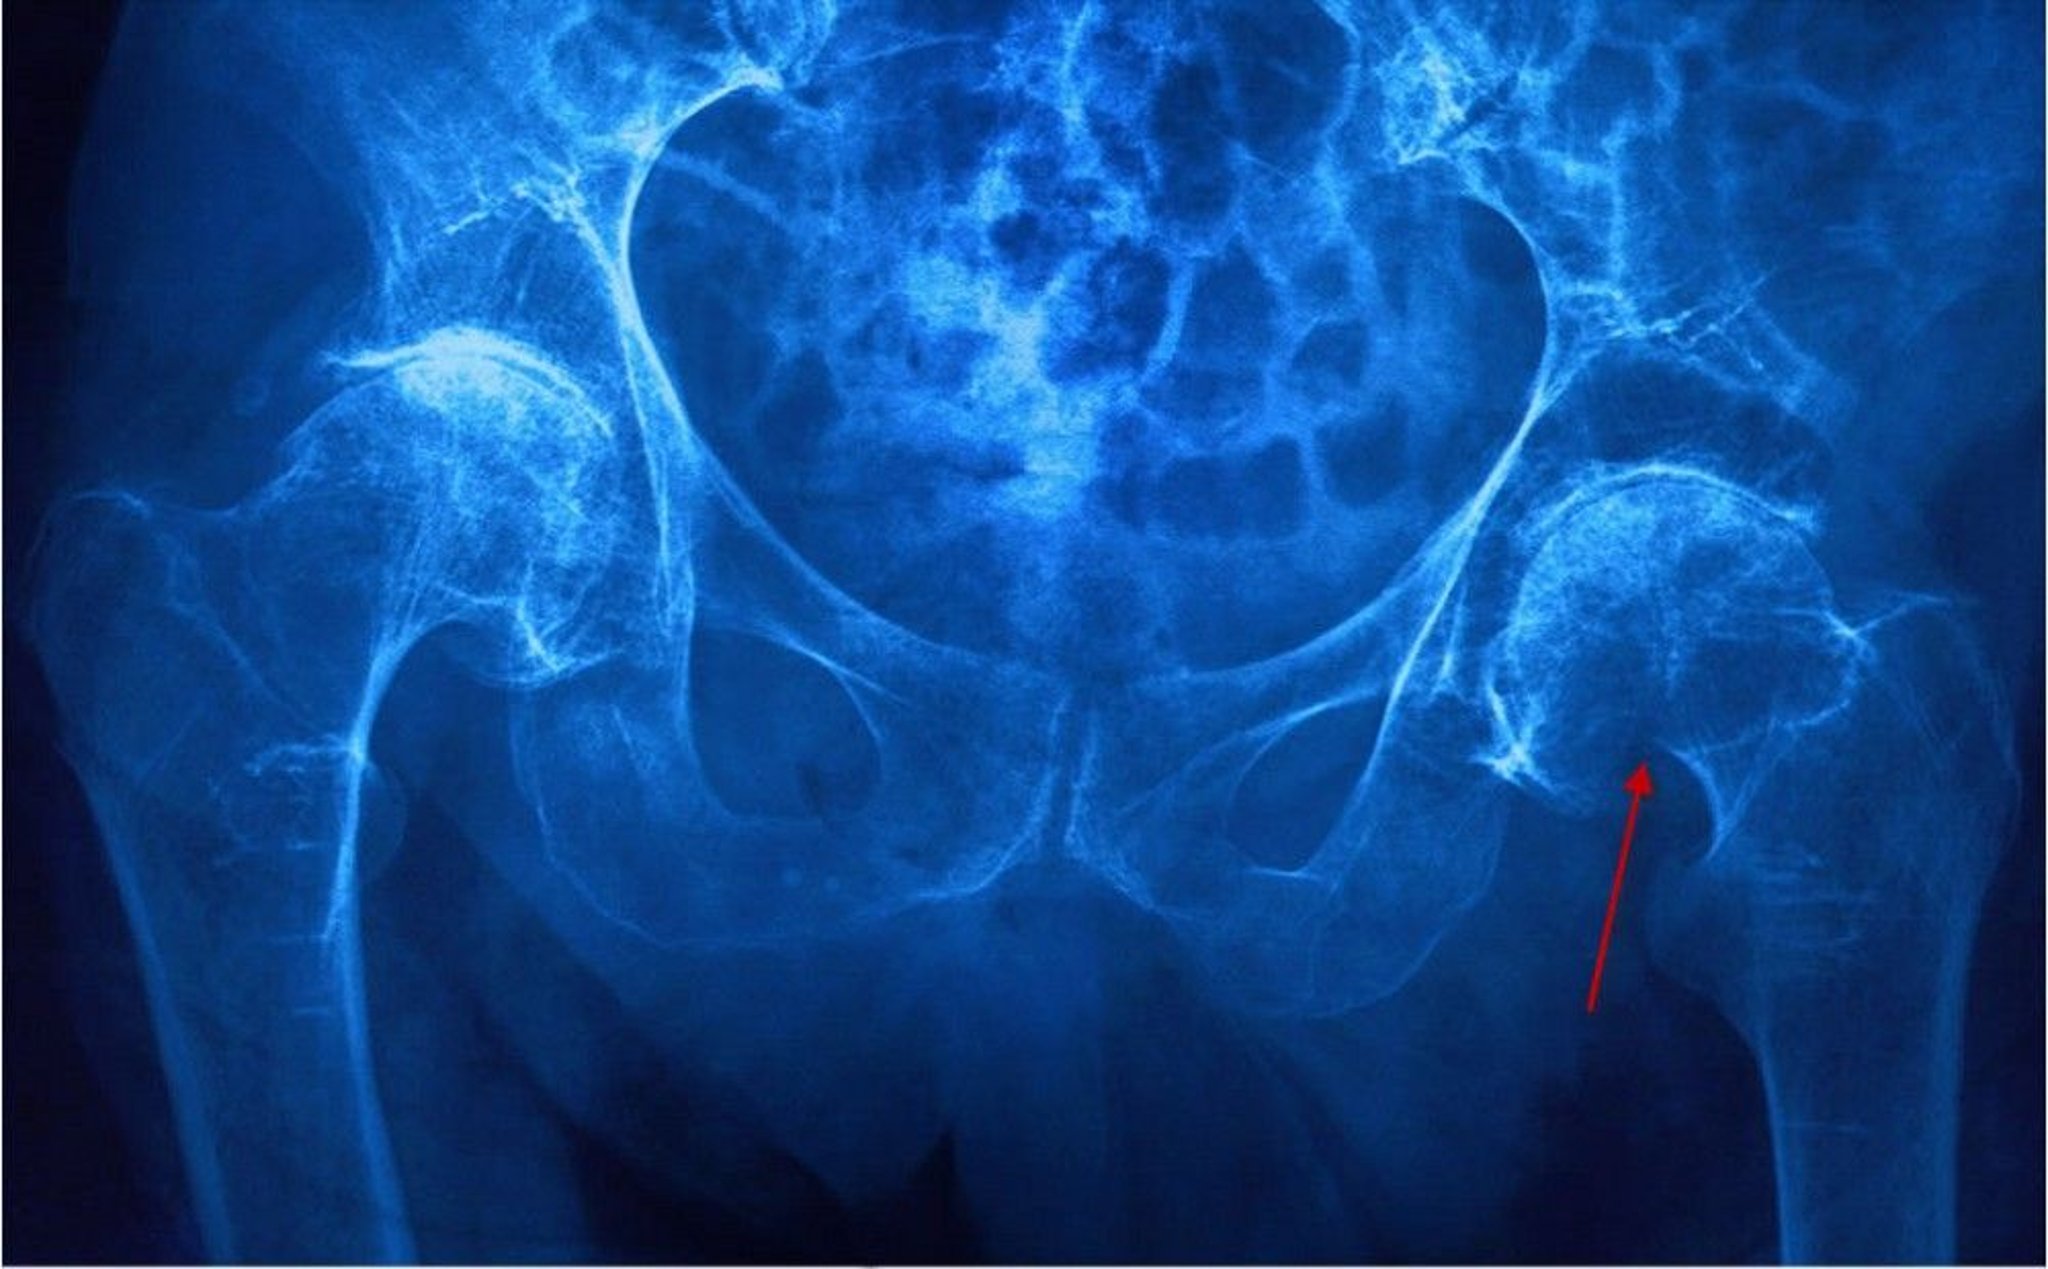

Femoral Neck Fracture

This radiograph shows a left femoral neck (subcapital) fracture evidenced by a shortened femoral neck and disruption of the cortex (arrow).